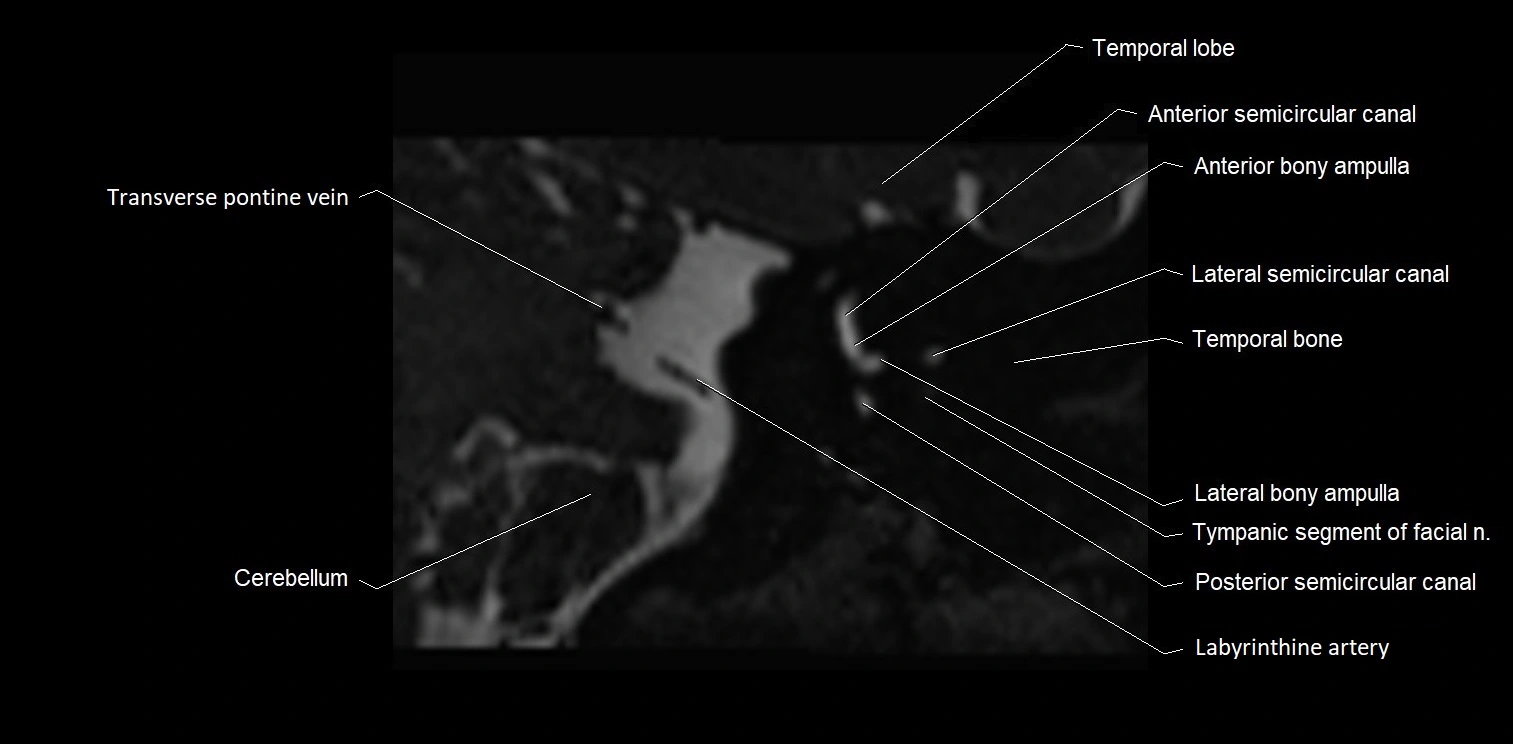

MRI images

image